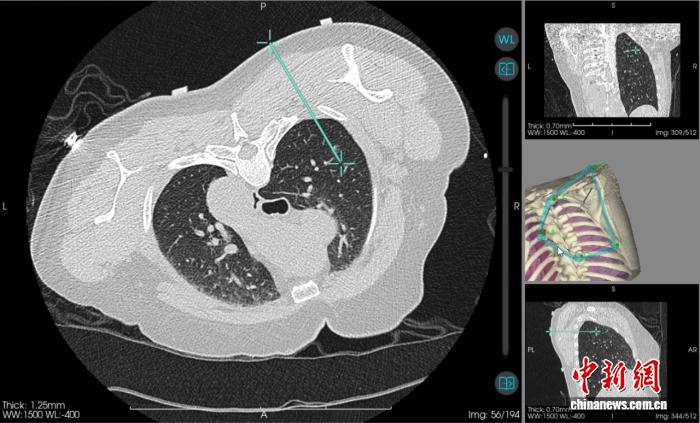

图为机器人引导下实际穿刺路径。广西医科大学第一附属医院 供图当天,该院心胸外科主任阳诺带领消融团队开展手术。他介绍,在术前,穿刺手术机器人系统基于患者CT影像,能自动构建详细的肺部3D立体模型,清晰呈现结节与周围血管、气管等重要组织的位置关系。

“它就像一位‘智能导航员’,精准规划穿刺路径、角度与深度,有效避开血管、气管等重要组织结构,将误差控制在毫米级。”阳诺说。